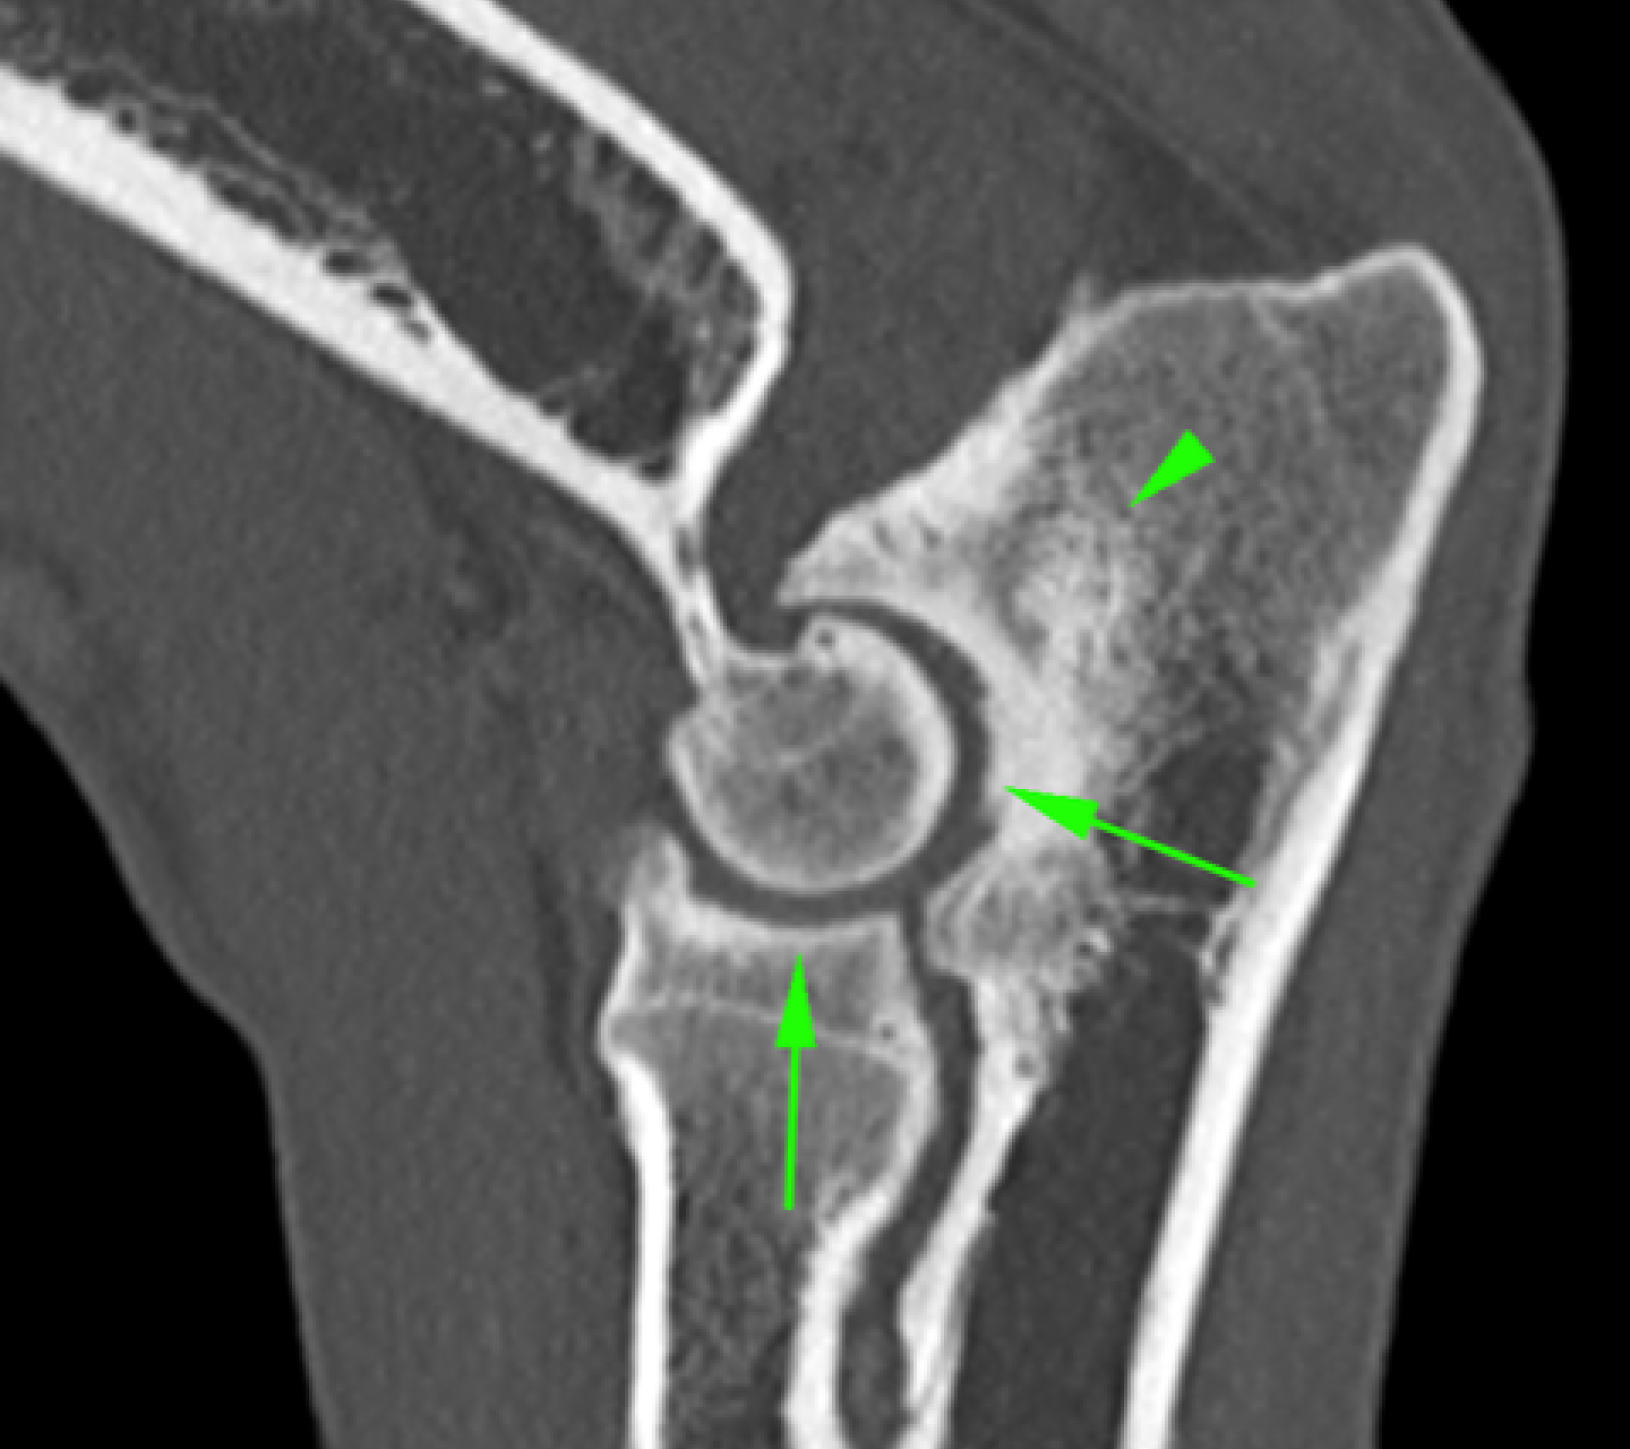

La Tomografía computerizada (CT) o TAC es la técnica por imagen de elección. El procesado avanzado de la imagen nos permitirá visualizar finos cortes de la anatomía y detectar pequeñas lesiones (por ejemplo, fragmentación del proceso coronoides), las cuales son difíciles de diagnosticar en radiografías convencionales.

• Enfermedad del proceso coronoides medial (EPCM): se trata de la condición más encontrada de todas las que se incluyen en la displasia de codo. El proceso coronoides puede encontrarse malformado, fisurado e incluso fragmentado. Como resultado de esta enfermedad y del roce anormal de dicha estructura con la superficie articular del cóndilo humeral medial, se produce un desgaste acelerado de las superficies cartilaginosas del aspecto medial del codo dando lugar al Síndrome del compartimento medial, el cual se ve favorecido por la sobrecarga que soporta la región interna de la articulación en condiciones fisiológicas.

• No unión del proceso ancóneo (NUPA): el proceso ancóneo del cúbito, que en muchas ocasiones posee un núcleo de osificación independiente al resto del hueso, no se fusiona después de los 5 meses de edad. En muchas ocasiones se relaciona con la incongruencia articular.